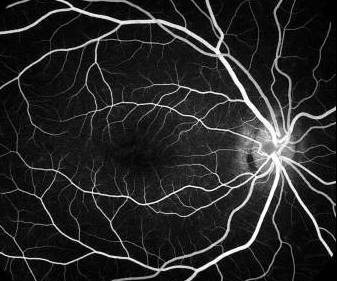

Dark choroid in a patient with early Stargardt's disease.